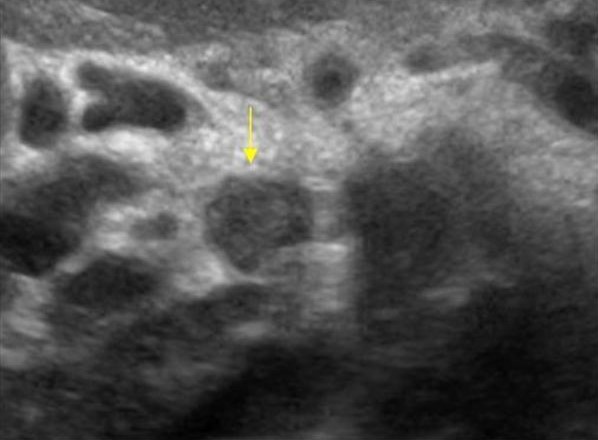

УЗИ диагностика кольцевидной поджелудочной железы: что важно знать